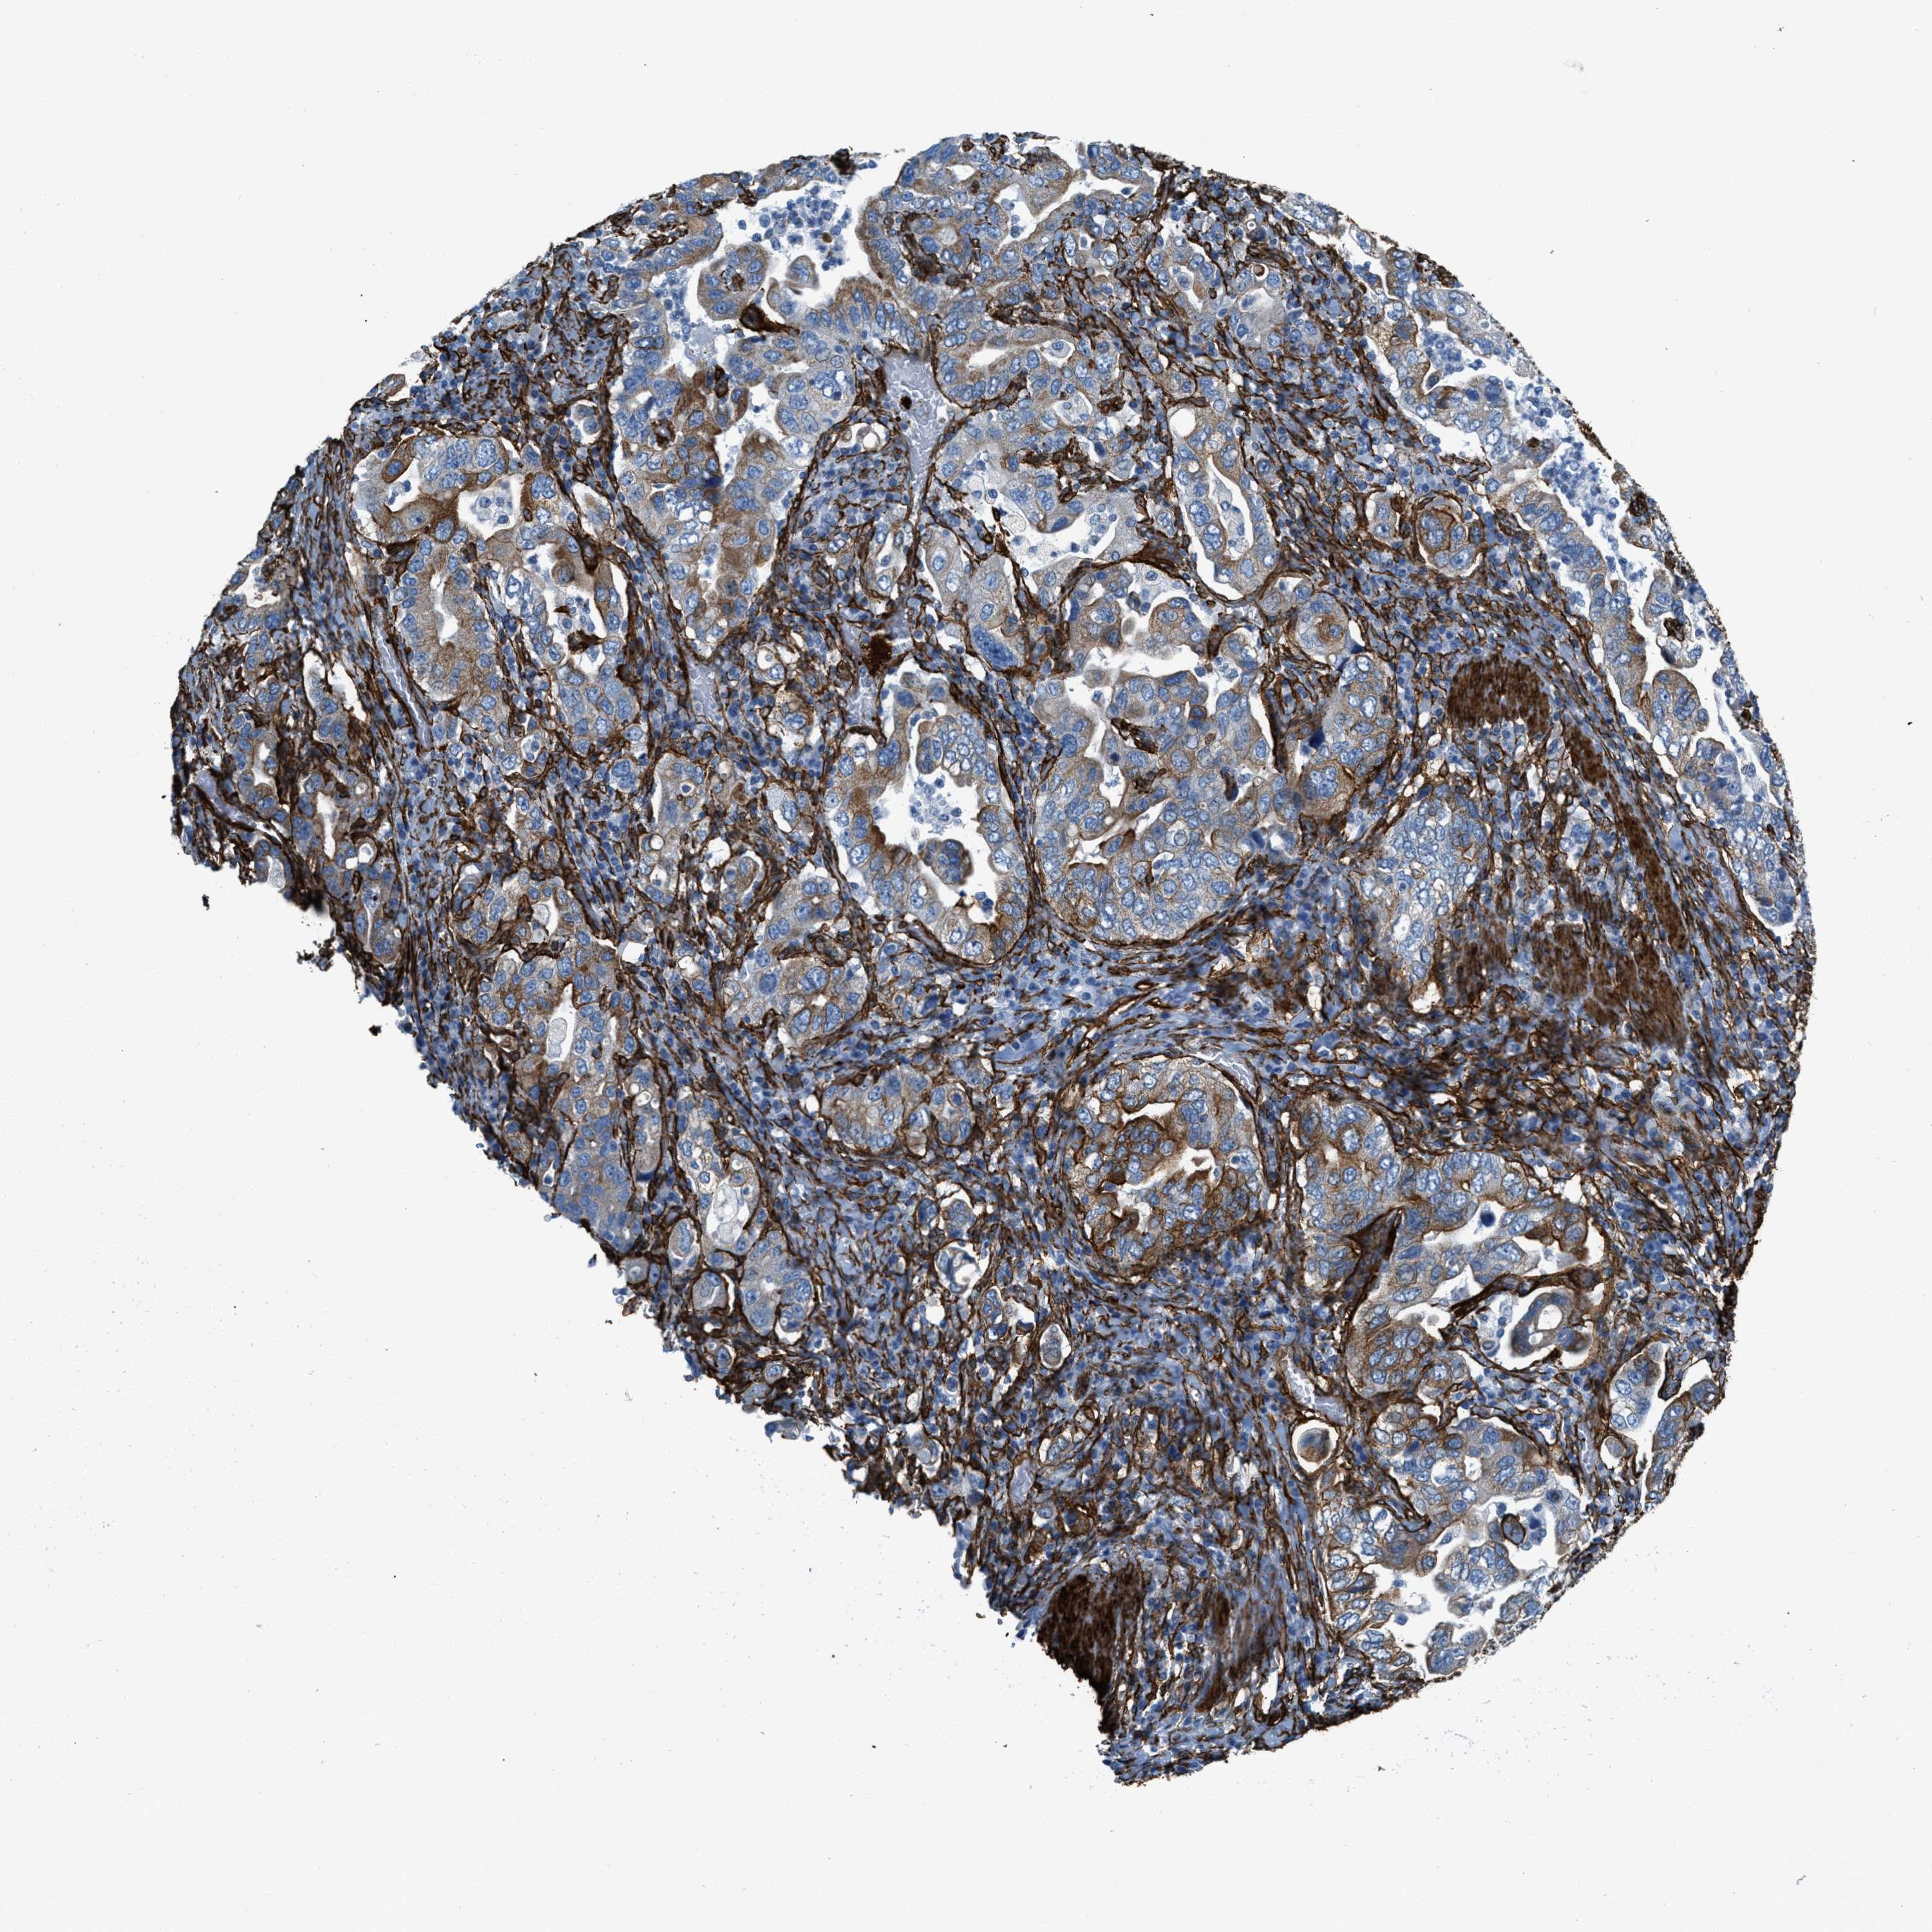

STOMACH CANCER - Protein expressioni

A mouse-over function shows sample information and annotation data. Click on an image to view it in a full screen mode. Samples can be filtered based on level of antibody staining by selecting one or several of the following categories: high, medium, low and not detected. The assay and annotation is described here.

Note that samples used for immunohistochemistry by the Human Protein Atlas do not correspond to samples in the TCGA dataset.

Antibody stainingi

Antibody staining in the annotated cell types in the current human tissue is reported as not detected, low, medium, or high, based on conventional immunohistochemistry profiling in selected tissues. This score is based on the combination of the staining intensity and fraction of stained cells.

Each image is clickable and will lead to virtual microscopy that enables deeper exploration of all samples and also displays staining intensity scores, fraction scores and subcellular localization as well as patient and tissue information for each sample.

Antibody HPA008066

Antibody HPA017330

Antibody CAB000006

Staining

High

Medium

Low

Not detected

Intensity

Strong

Moderate

Weak

Negative

Quantity

>75%

75%-25%

<25%

None

Location

Nuclear

Cytoplasmic/membranous

Cytoplasmic/membranous,nuclear

Adenocarcinoma, NOS